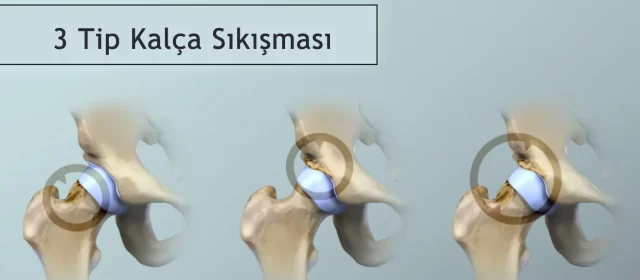

Kalça Sıkışması (Femoroasetabular Sendrom) Nedir?

Kalça sıkışması (Femoroasetabular Sendrom – FAI), kalça eklemini oluşturan kemiklerin birbirine uygunsuz şekilde temas etmesiyle ortaya çıkan bir eklem rahatsızlığıdır. Kalça eklemi topuz (femur başı) ve soket (asetabulum) yapılarından oluşur. Normalde bu iki yapı birbiriyle uyum içinde çalışırken, kemik yüzeylerinde oluşan anormal çıkıntılar hareket sırasında birbirine sürtünmeye neden olur. Bu

Kalça Ağrısı Femoroasetabular Sıkışma (FAS / FAI) Nedir?

Femoroasetabular sıkışma (FAS, İng. FAI), kalça ekleminde femur başı (topuz) ile asetabulumun (soket) anormal temas etmesi sonucu gelişen, ağrı ve zamanla kıkırdak hasarına yol açabilen bir durumdur. Tekrarlayan sürtünme ve çarpışma labrum yırtığına, kıkırdak bozulmasına ve uzun vadede erken koksartroza (kalça kireçlenmesine) neden olabilir. Özellikle genç, aktif ve sporcu popülasyonunda